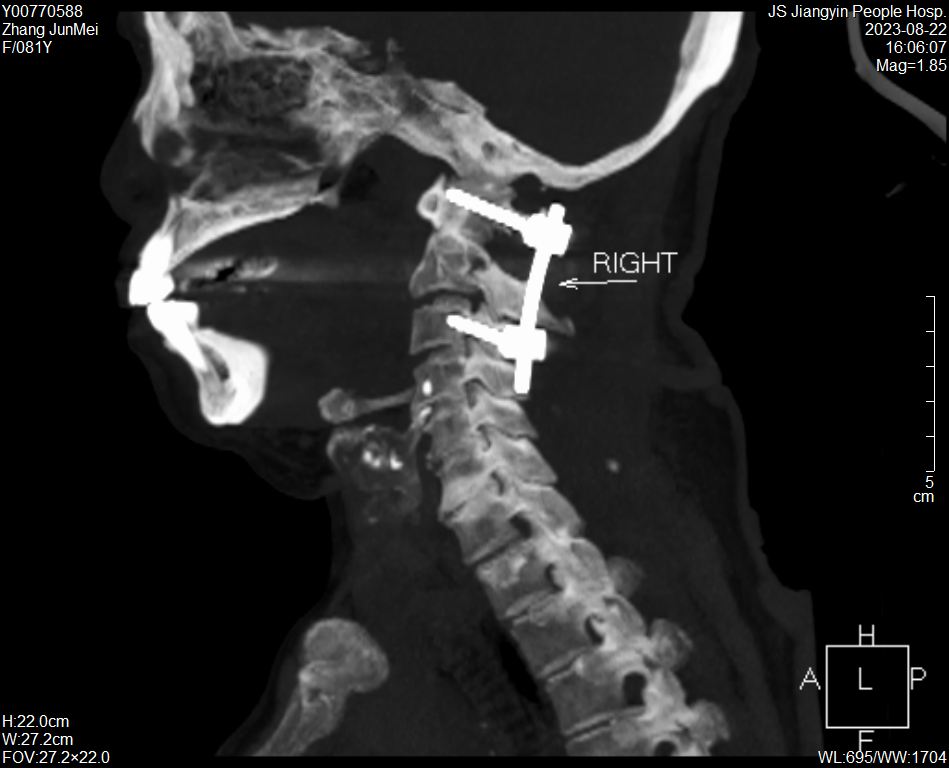

醫護團隊根據患者病情,制定了詳細的診療方案及手術風險預案,與患者和家屬充分溝通后,為張奶奶行頸后入路寰樞椎復位內固定術,手術過程順利。

張奶奶術后CT

術后第2天,老人就佩戴頸椎支具下床活動。目前,張奶奶病情恢復良好,穩步康復中。